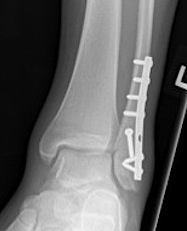

ORIF fibular

- ensure medial joint space fully reduced

- may need to open medial joint / removed osteochondral fragments / deltoid ligament

ORIF options

Plate - 1/3 tubular / DCP / anatomic locking plate

Fibular nail

ORIF